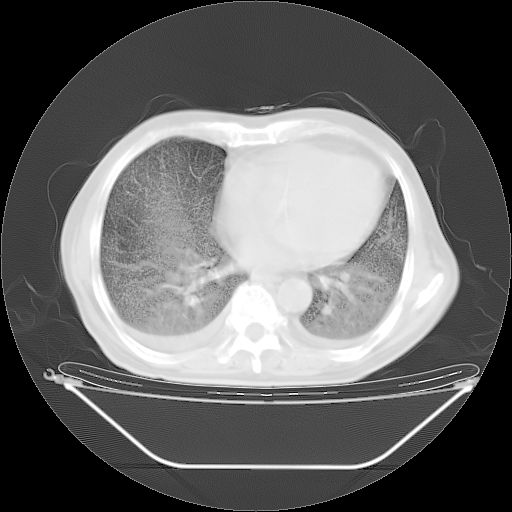

今天复查肺部CT,发现双肺广泛磨玻璃样改变。所以我把3月19日和5月9日相隔50天的肺部CT上传。请大家会诊。

2009年3月19日肺部CT片。

2009年3月19日肺部CT